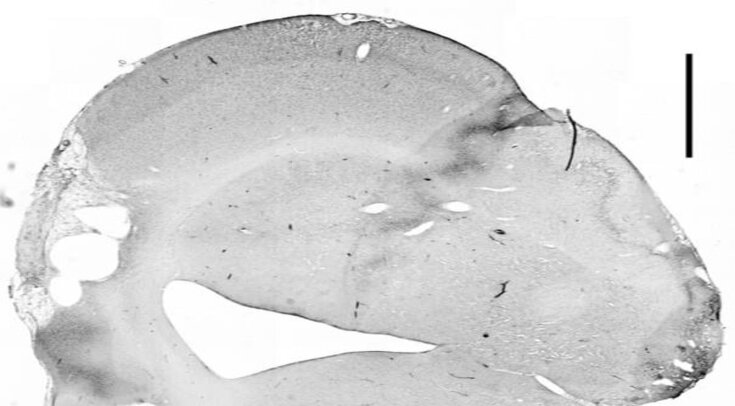

Мозг крыс исследовали через 24 часа при однократном введении антител и через 72 часа при трехкратном (один раз в день) введении через нос. Мозг изучали с помощью иммуногистохимического анализа. При однократном введении одного миллиграмма антител через сутки в мозгу крыс ученые обнаруживали антитела в обонятельных луковицах, моторной коре, мозолистом теле, гиппокампе, мозжечке и в некоторых областях ствола мозга. Ежедневное введение антител через нос в течение трех дней приводило к более высоким уровням антител во всех областях ЦНС.

Daphne Correa et al. / PNAS, 2023

Эти результаты показывают, что моноклональные антитела против Nogo-A при их введении через нос проникают в ткань мозга и клетки, экспрессирующие антиген Nogo-A.